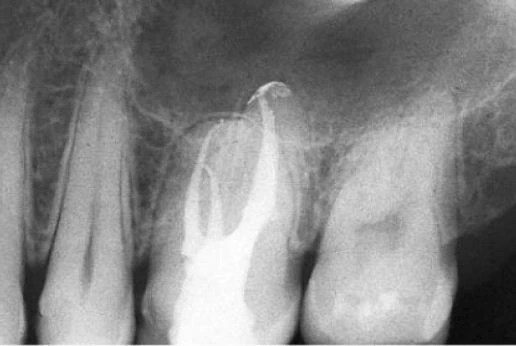

Về mặt giải phẫu học, răng cối nhỏ thứ nhất trên có thể có hình dạng hoàn toàn khác. Ống tủy cong hình lưỡi lê ở 1/3 chóp chân răng là một dạng điển hình. Hiếm khi tìm thấy một ống tủy đơn, hình elip trong một chân răng; thường gặp hai ống tủy giao nhau ở 1/3 giữa với hai lỗ chóp trong một chân răng (38%) hoặc hai ống tủy (thường cùng chiều dài) ở trong hai chân răng riêng biệt (60%). Hiếm hơn nữa có thể thấy ba chân răng với ba ống tủy và những lỗ chóp riêng biệt, chiếm 6% theo Carns và Skidmore , và 5% theo những tác giả khác. Trong những trường hợp này, RCN có hình dạng như răng cối lớn. Một ống tủy rộng hơn ở phía trong và hai ống nhỏ hơn ở phía ngoài, một ở phía gần và một ở phía xa (hình 11.46). Điều trị nội nha tốt hay không phụ thuộc vào việc tạo xoang tủy có đúng hay không: răng cối nhỏ trên với ba ống tủy thì cần tạo một xoang tủy có hình dạng chữ “T” với sự mở rộng theo chiều gần xa ở phần ngoài của xoang truyền thống. Sự thay đổi này cho phép tạo một đường vào tốt cho cả hai ống tủy ngoài. Nếu ba chân răng phân kỳ, ta có thể thấy được trên phim X-quang trước điều trị. Nếu ba chân răng chụm hoặc chồng lên nhau (hình 11.47A), ta có thể biết được trong lúc điều trị. Nha sĩ có thể nghi ngờ có hai ống tủy ngoài không chỉ nhờ vào sự hiện diện của 2 miệng ống tủy (thường không nhận ra hai miệng ống tủy riêng biệt), mà còn nhờ vào hướng của cây trâm thăm dò khi nó đi vào một trong hai ống tủy, hoặc hình dung trên phim X-quang thấy hình ảnh dị dạng nhưng những đường nét chung của chân răng vẫn bình thường [ví dụ: hoàn toàn nằm về phía gần (hình11.47 B)], ta có thể nghi ngờ còn một ống tủy ngoài thứ hai nữa mà hướng của nó nằm về phía xa hơn so với ống thứ nhất (hình 11.47 C, D).

Hình 11.46. A. Phim sau điều trị của răng #14 với ba ống tủy ở ba chân răng khác nhau. B. Trên cùng một bệnh nhân,hình ảnh X-quang răng #24. C. Hình ảnh X-quang trước điều trị của răng #24 với hình ảnh chân răng chồng lên nhau. D. Một góc chụp khác sau điều trị cho thấy hình ảnh ba ống tủy trong ba chân riêng biệt. E. Sau hai năm. F. Phim sau điểu trị của răng #14. Răng có ba chân: chân trong thẳng, hai chân ngoài nghiêng xa. G. Sau 3,5 năm.

Hình 11.47. A. Phim trước điều trị răng #14: Chân răng chồng lên nhau, không dễ nhận ra ba ống tủy. B. Dụng cụ đầu tiên được đừa vào miệng ống tủy (dường như là ống ngoài), hình ảnh dụng cụ đi theo một hướng bất thường so với hình ảnh chân răng. Nhìn kỹ thấy nó chuyển hướng về phía gần: dụng cụ đã đi vào ống gần ngoài. C. Uốn cong dụng cụ về phía xa rồi đưa vào cùng miệng ống tủy này, nó tự động đi vào ống xa ngoài. D. 34 tháng sau, phim X-quang cho thấy sự hiện diện của ba ống tủy.